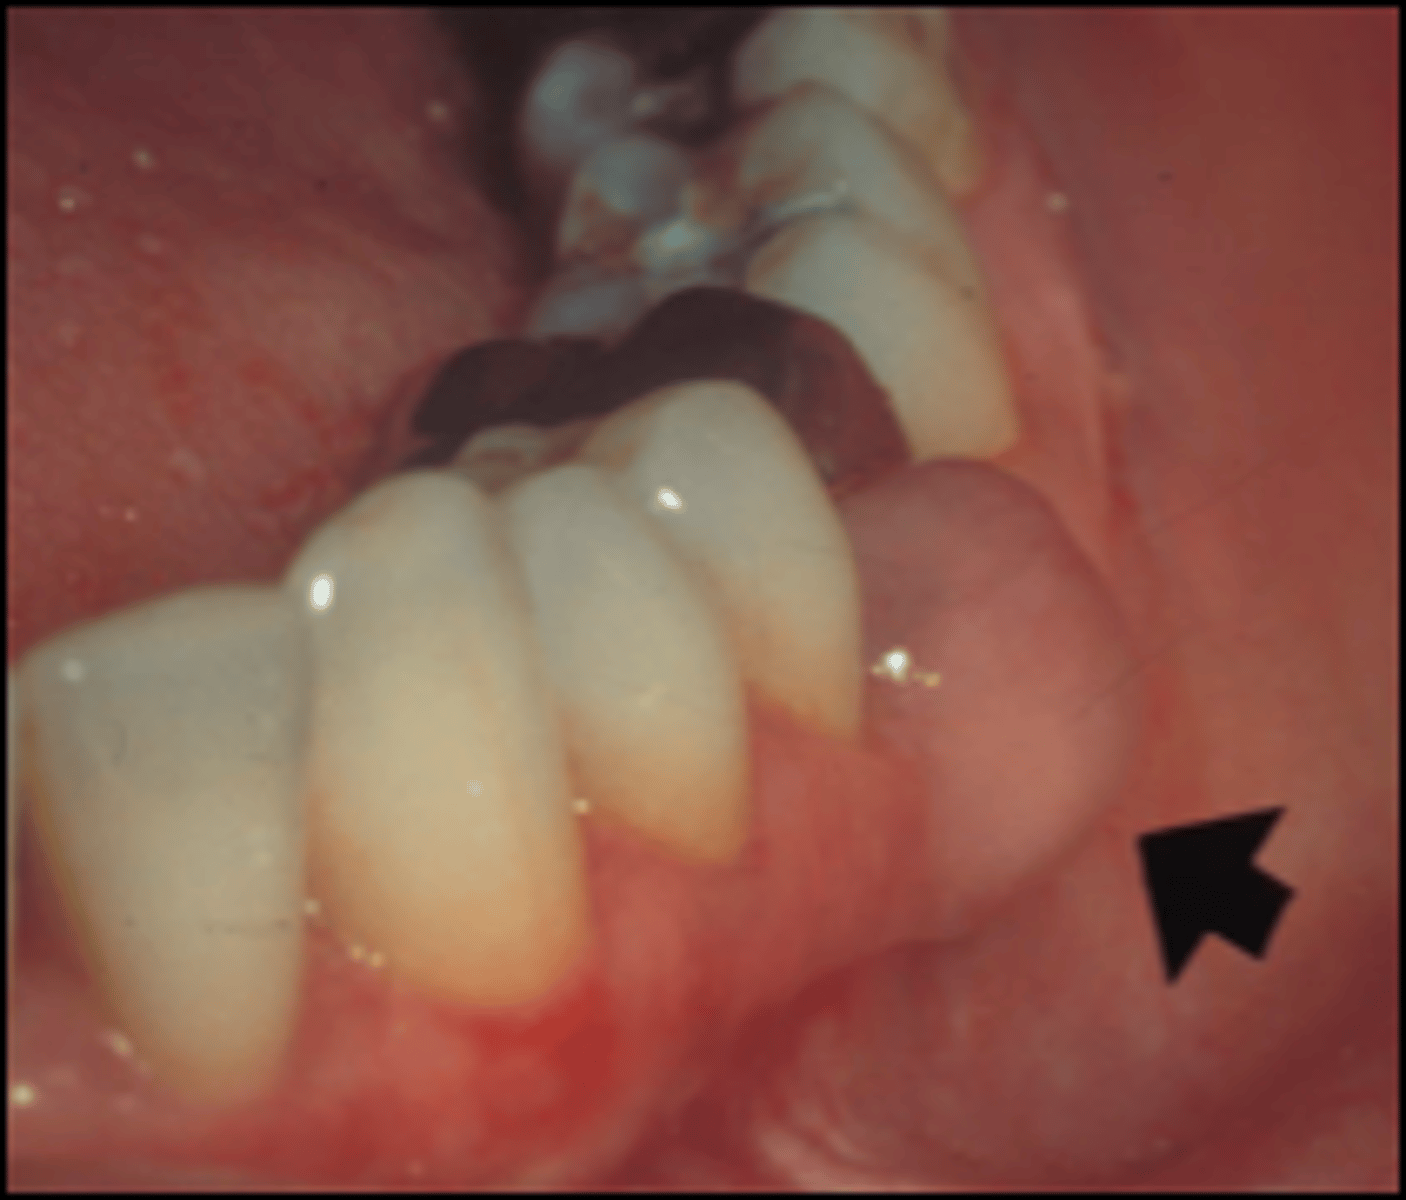

What is a peripheral ameloblastoma?

ameloblastoma of gingiva

⢠central = lesion in bone, peripheral = lesion in soft tissues

⢠RARE presentation of ameloblastoma

ā most odontogenic cysts/tumors can have peripheral presentations

⢠little to no bony involvement

⢠not as invasive

⢠treatment = surgical excision

⢠prognosis = excellent - recurrence is rare